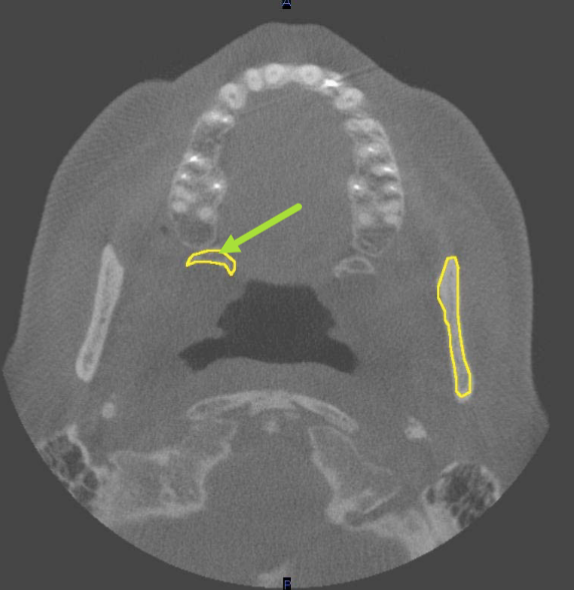

identify the structure indicated by the ARROW

incisive foramen

what is indicated by the YELLOW

middle turbinates/concha